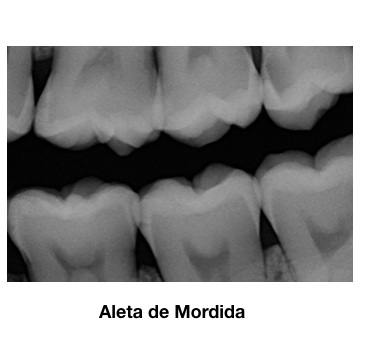

Redefinio la técnica Bisectriz y presento la técnica de aleta de molde.